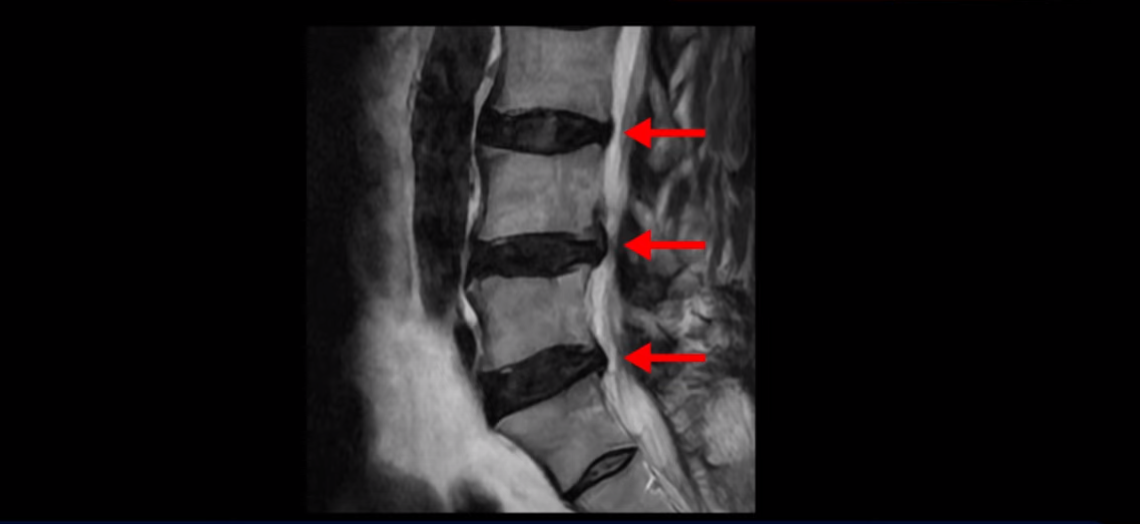

이분 MRI를 보면 허리 세 마디 정도의 퇴행성 디스크가 있고

20251020_1

4번 5번 마디에는 중심성 협착이 있습니다.

20251020_2

후관절과 황색인대가 두꺼워져 있어서 척추관이 좁아져 있습니다.